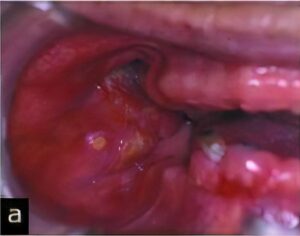

悪性腫瘍

口腔内に発生する悪性腫瘍では、扁平上皮癌という口腔内の粘膜から発生する癌が最も多いのが特徴です。その他には、唾液腺から発生するものや骨肉腫などの内部の組織から発生する悪性腫瘍もあります。

悪性腫瘍を認めた場合には、病変部も含めた全身の精密検査(全身状態、転移の有無、重複癌(他の組織に癌が発生する)の確認)が必要になります。治療には、手術、抗がん剤による化学療法、放射線療法を単独あるいは組み合わせて行います。

治療後には定期的な検査が必要になり、当院では悪性腫瘍治療を行った病院の指示の元、歯科治療を行います。

悪性腫瘍を歯周病や口内炎、義歯による傷などと思い込み、長期間放置し、腫瘍が大きくなてから歯科医院を受診するケースが多いようです。口腔内の悪性腫瘍だけに限定される話ではありませんが、早期発見・早期治療が重要です。